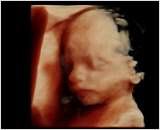

d.h. pränataler Ultraschall (Messung der Nackendicke, Organscreening) einerseits, andererseits kann noch eine Untersuchung mittels 4D-Ultraschall durchgeführt werden,

wo ein dreidimensionales Bild von Ihrem Kind angefertigt werden kann.

Dieses ermöglicht die Diagnostik einiger Fehlbildungen wie etwa der Lippen-Kiefer-Gaumenspalte, andererseits kann so das erste "Foto" von Ihrem noch ungeborenen Kind gemacht werden, was die Mutter-Kind-Beziehung zusätzlich fördert.